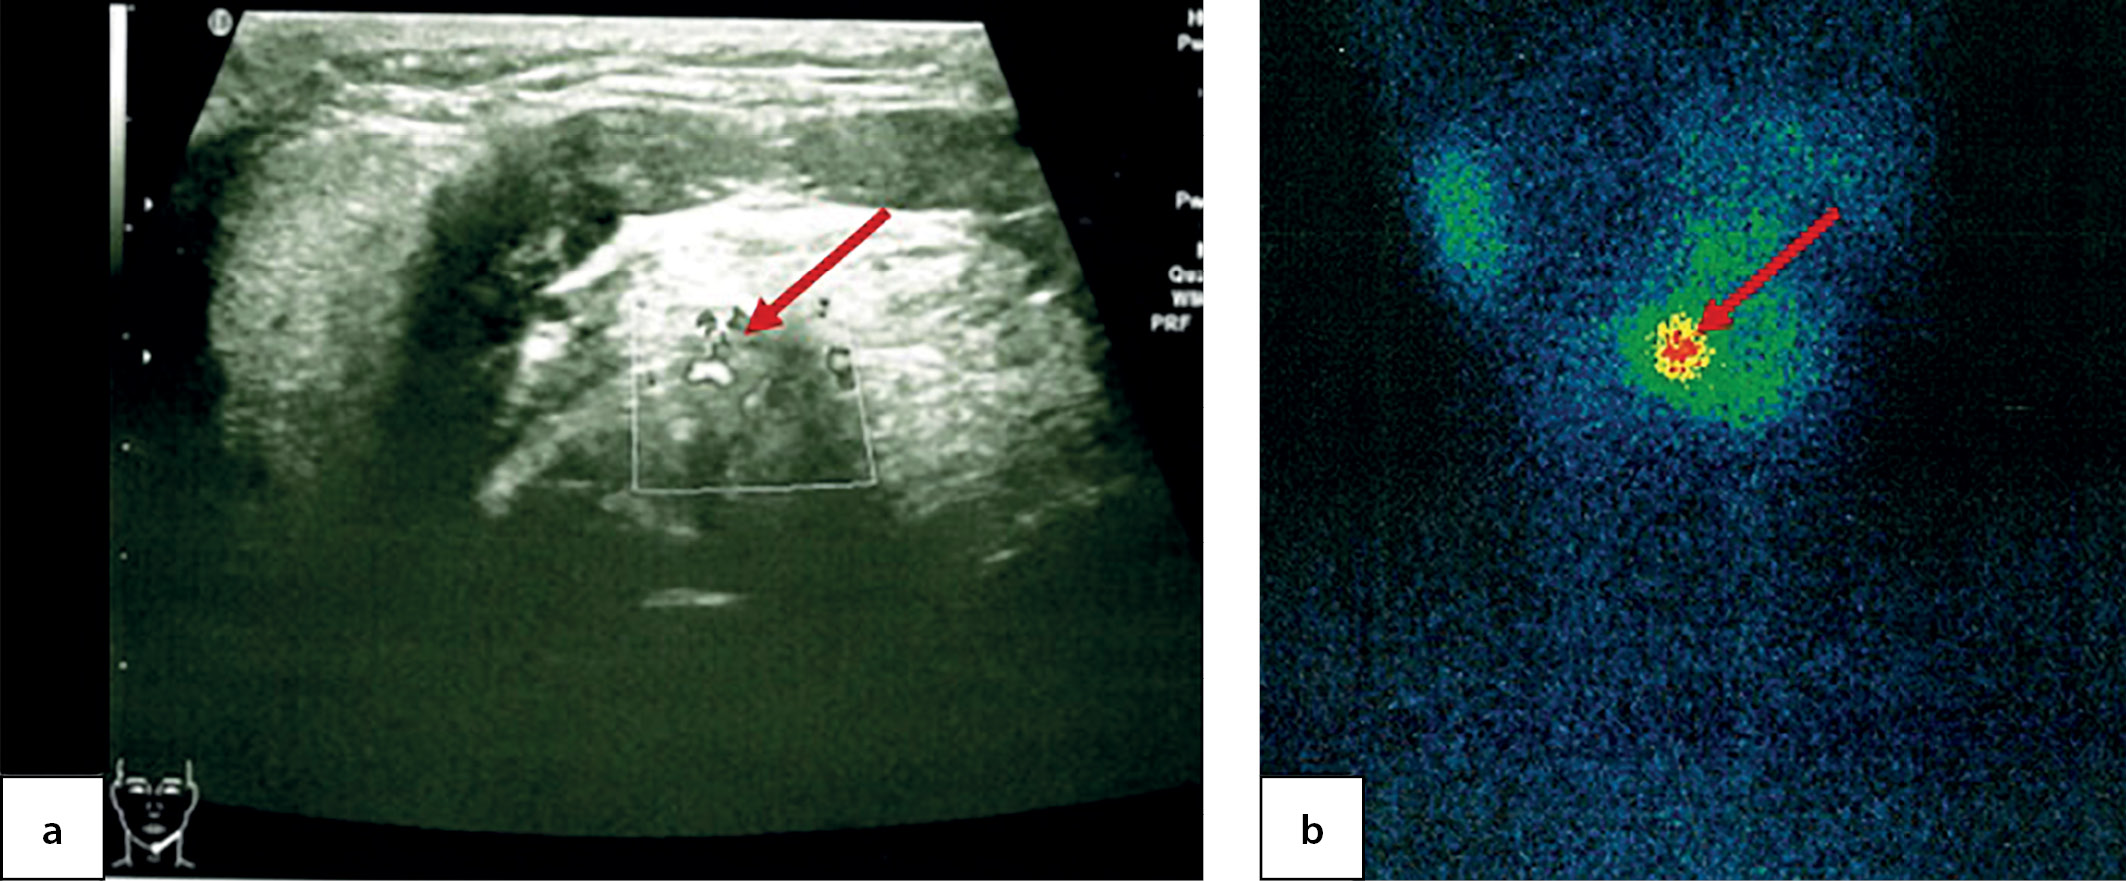

An ultrasound imaging found a round-shaped thyroid tissue in the root of tongue plane; it had low echoicity, homogenous structure and active vascularisation when observed through colour Doppler imaging and power Doppler imaging (Figure 6, a & b). Moreover, acyst was identified in the right-hand side of anterior neck with dimensions 0.4×0.3×0.2 cm. A thyroid scintiscan confirmed the presence of ectopic thyroid tissue in the root of tongue with dimensions 1.4×1.5×1.8 cm (Figure 6, c). The dose of levothyroxine for this patient was increased to 1.3 mg/kg/day.

Figure 6. Ectopic thyroid tissue in the root of tongue in a 7.5-year-old patient as identified through: ultrasound imaging in longitudinal view (a); power Doppler imaging in transverse view (b); and thyroid scintiscan with 99mТc pertechnetate in the planar mode (c)